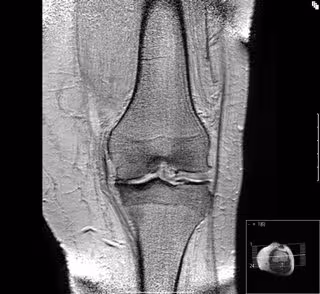

Archivo - Artrosis de rodilla

Archivo - Artrosis de rodilla - UAM - Archivo